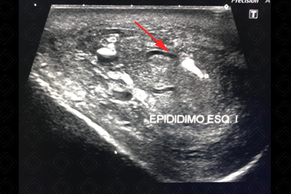

Descrição das figuras: Ultrassonografia da bolsa escrotal. Epidídimo esquerdo com volume muito aumentado e com hipervascularização ao Doppler colorido, compatível com epididimite aguda à esquerda.

• Ultrassonografia da bolsa escrotal: o epidídimo apresenta volume aumentado, sua ecogenicidade pode estar aumentada ou reduzida, mas em geral sempre heterogêneo e com fluxo aumentado no estudo com Doppler colorido. Edema de bolsa escrotal e uma hidrocele reacional comumente estão presentes. A inflamação pode atingir o testículo por contiguidade, levando a um quadro de orquiepididimite (figuras acima). Exame de escolha para população pediátrica ou adulta.